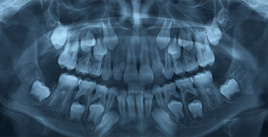

Another way to learn about Chalky Molars is to do "Lots Of Looking" with Special Machines. Some of the machines are called Microscopes. They work like Magnifying Glasses to make small things really big. Other machines grind the teeth into thin slices or dust, and then make pictures of their ingredients. All these Experiments let Scientists see what is different about Chalky Teeth. On the Right you can see three different pictures made with Normal and Wonky Teeth. If you want to see the Special Machine that made the picture, and the Tooth Scientist that used the machine, then click on each picture or use the link below.